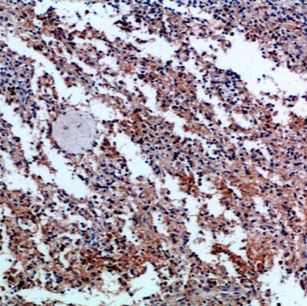

Product Image |

| IHC | 1/50-1/100 |